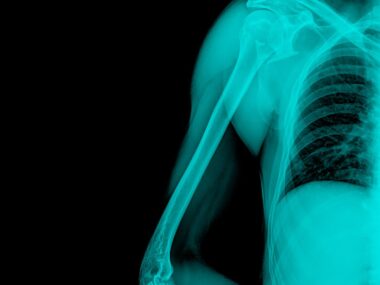

I always knew I wanted to breastfeed. It felt like something primal, something deeply rooted in me. But with Gaucher disease and a preexisting diagnosis of osteoporosis at just 27 years old, I also knew it could get complicated, as pregnancy and nursing can further deplete bone density.